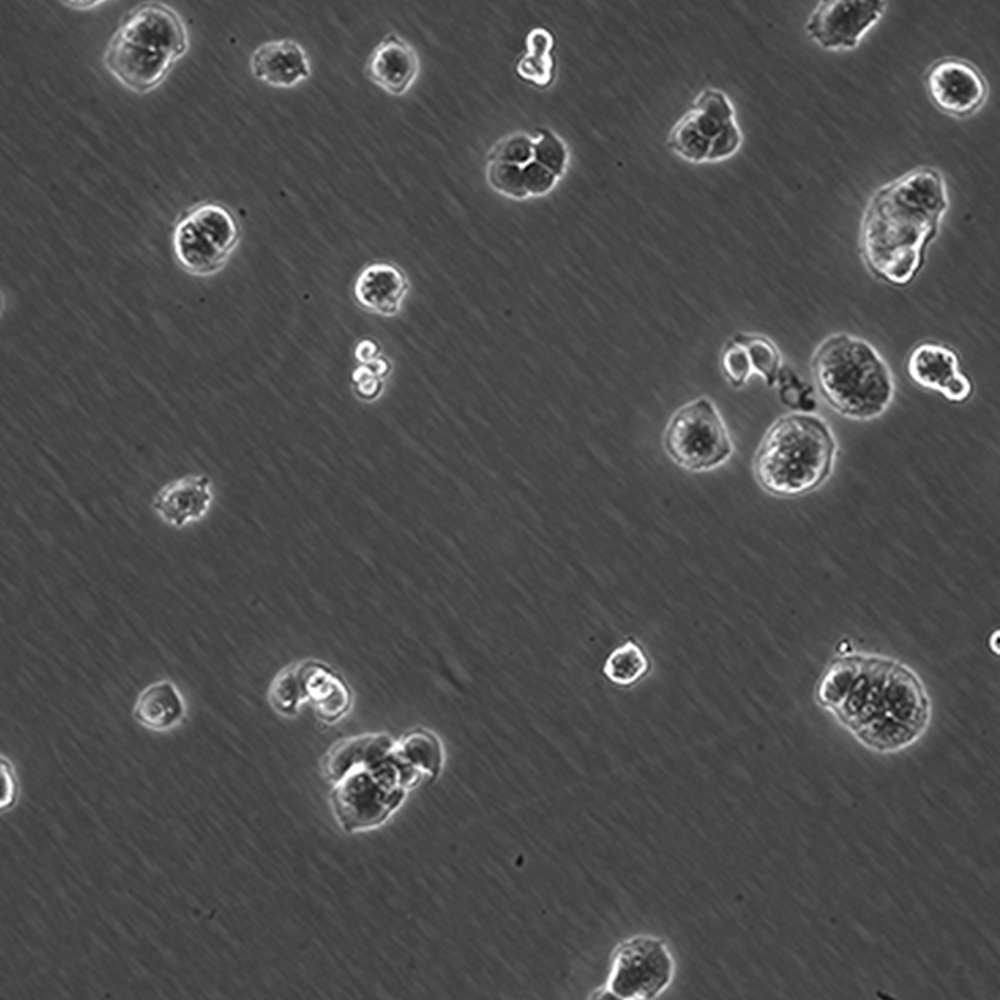

WiDr

產品名稱 WiDr

中文名稱 人結直腸癌細胞

組織來源 結腸癌;女性

生長特性 貼壁

細胞污染 HIV-1、 HBV、HCV、支原體、細菌、酵母和真菌檢測陰性。

培養基 EMEM(MEM+NEAA),90%;FBS,10%;雙抗。

傳代方法 1:2-1:4

培養條件 Atmosphere: Air, 95%; CO2, 5%。Temperature: 37℃

細胞傳代步驟 如果細胞密度達80%-90%,即可進行傳代培養。1. 棄去培養上清,用不含鈣、鎂離子的PBS潤洗細胞1-2次。2. 加2ml消化液(0.25%Trypsin-0.53mM EDTA)于培養瓶中,置于37℃培養箱中消化1-2分鐘,然后在顯微鏡下觀察細胞消化情況,若細胞大部分變圓并脫落,迅速拿回操作臺,輕敲幾下培養瓶后加少量培養基終止消化。3. 按6-8ml/瓶補加培養基,輕輕打勻后吸出,在1000RPM條件下離心4分鐘,棄去上清液,補加1-2mL培養液后吹勻。4. 將細胞懸液按1:2到1:5的比例分到新的含8ml培養基的新皿中或者瓶中。

復蘇細胞步驟 將含有1mL細胞懸液的凍存管在37℃水浴中迅速搖晃解凍,加入4mL培養基混合均勻。在1000RPM條件下離心4分鐘,棄去上清液,補加1-2mL培養基后吹勻。然后將所有細胞懸液加入培養瓶中培養過夜(或將細胞懸液加入10cm皿中,加入約8ml培養基,培養過夜)。第二天換液并檢查細胞密度。

細胞凍存步驟 待細胞生長狀態良好時,可進行細胞凍存。下面T25瓶為例;? 1.細胞凍存時,棄去培養基后,PBS清洗瓶底1-2次后加入1ml胰酶,細胞變圓脫落后,加入2ml完全培養基終止消化,可使用血球計數板計數。 2.1000RPM離心5分鐘去掉上清。用血清重懸浮,加DMSO至最終濃度為10%。加入DMSO后迅速混勻,按每1ml的數量分配到凍存管中,注意凍存管做好標識。本公司按每個凍存管細胞數目大于1X106個細胞凍存。3.將凍存管置于程序降溫盒中,放入-80度冰箱,至少2個小時以后轉入液氮灌儲存。記錄凍存管位置以便下次拿取。

細胞凍存 Freeze medium: FBS/NBS, 92%;DMSO, 8%(for reference)Storage temperature: liquid nitrogen vapor phase

細胞運輸 干冰運輸(2ml凍存管)或活細胞運輸(T25細胞瓶)